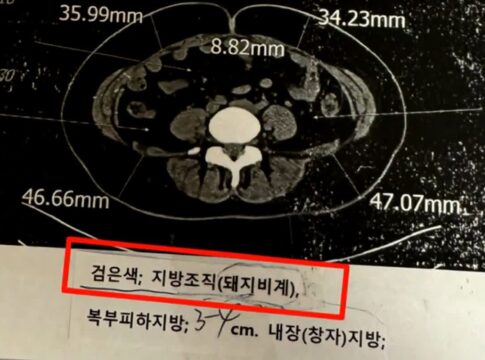

「嫌なら二度と来るな」肥満患者にCT画像を見せながら「豚の脂身」と言及する韓国人医師

引用=JTBC 「事件班長」医師が患者の脂肪組織を「豚の脂身」と表現し、強い非難を浴びている。22日、韓国の番組JTBC 「事件班長」によると、A氏は「甲状腺機能亢進症」と診断され、地元の有名病院に入院中、驚くべき出来事を経験したという。A氏は、動悸や息切れを感じ、循環器内科を ...

道路に突然現れた、綺麗に横たわる「遺体」…まさかの場所から落下した遺体だった 引用=Newsisポーランドで、霊柩車で運ばれていた遺体が道路に落下し、周辺が交通渋滞に陥る事故が発生した。21日(現地時間)、英国のデイリー・メール、ガーディアンなど複数のメディアによると、この事件は18日午後7時頃、ポーランドのスタロバ・ボラ市の市街地で発生した。目撃者の男 ... 「嫌なら二度と来るな」肥満患者にCT画像を見せながら「豚の脂身」と言及する韓国人医師 引用=JTBC 「事件班長」医師が患者の脂肪組織を「豚の脂身」と表現し、強い非難を浴びている。22日、韓国の番組JTBC 「事件班長」によると、A氏は「甲状腺機能亢進症」と診断され、地元の有名病院に入院中、驚くべき出来事を経験したという。A氏は、動悸や息切れを感じ、循環器内科を ...

「嫌なら二度と来るな」肥満患者にCT画像を見せながら「豚の脂身」と言及する韓国人医師 引用=JTBC 「事件班長」医師が患者の脂肪組織を「豚の脂身」と表現し、強い非難を浴びている。22日、韓国の番組JTBC 「事件班長」によると、A氏は「甲状腺機能亢進症」と診断され、地元の有名病院に入院中、驚くべき出来事を経験したという。A氏は、動悸や息切れを感じ、循環器内科を ... スパイ容疑をかけられた元人気アナウンサーがYouTubeチャンネルを開設、10年ぶりの発言に注目集まる 引用:星島日報2014年に中国当局に逮捕され、公の場から姿を消していた中国中央電視台(CCTV)の元有名アナウンサー芮成綱(47歳)氏が、最近YouTubeチャンネルを開設し、自身を巡る様々な噂はすべてフェイクニュースだったと主張した。22日(現地時間)、香港メディアである明報 ...